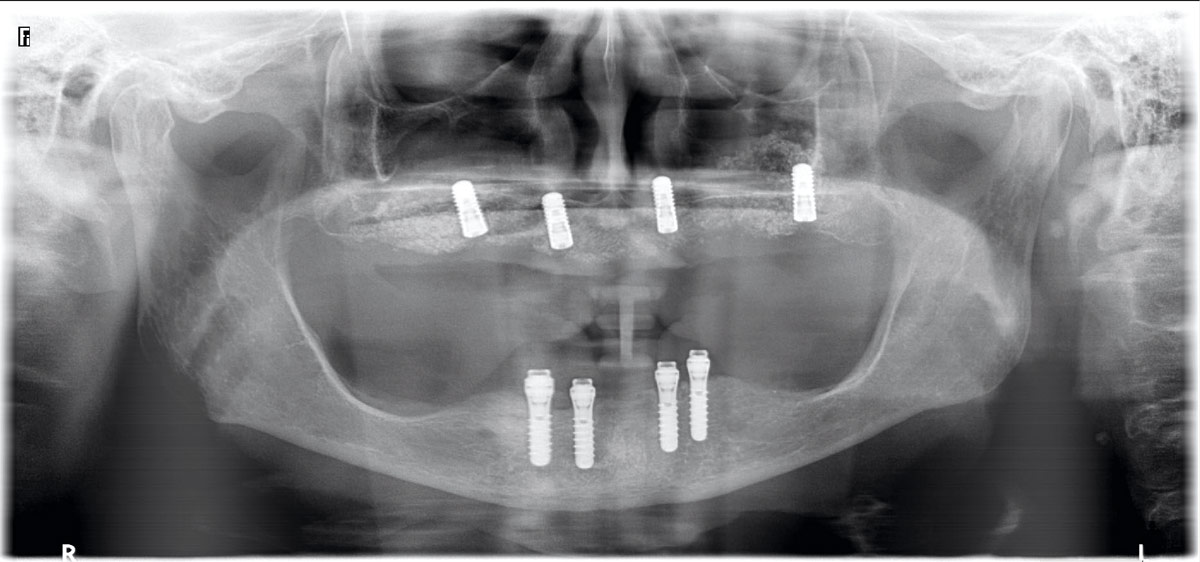

23/23 - Final x-ray one year after implantation 12/15/22/25

Full arch reconstruction of the maxilla with maxgraft® bonebuilder - Dr. M. Erbshäuser